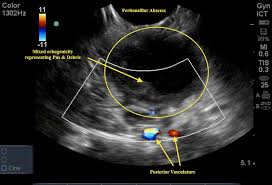

What Does Throat Cancer Look Like On An Ultrasound - Endoscopic Ultrasound Elastographic Lymph Node Evaluation - The ultrasound also tells us if the ovaries have a normal surface texture and whether there are cysts within the ovaries.. An ultrasound may show your doctor if a lump is filled with fluid or if it's solid. Within the first two days of the patient's arrival at our hospital. What does ovarian cancer look like on an ultrasound is not an easy question to answer. Your doctor will often use an ultrasound to create images of a fetus during pregnancy. If the cancer cells look like they might have come from the larynx or hypopharynx, an endoscopic exam and biopsy of these areas will be needed.

A solid one is more likely to have cancerous cells, but you'll still need more tests to find out. They may put a small, thin camera down your throat to look for problems, a procedure called a laryngoscopy. Ultrasound of the thyroid gland is necessary in the presence of the patient's complaints of a feeling of lump in the throat and difficulty swallowing, an unreasonable cough, increased nervousness and excitability, sleep disturbance, palpitations and tremors of hands, swelling, weight loss, prolonged subfebrile condition. What does ovarian cancer look like on an ultrasound is not an easy question to answer. Throat cancer refers to cancer of the voice box, vocal cords, and other parts of the throat, such as the tonsils and the oropharynx. Ultrasound technology is an important way to diagnose various conditions. For example, throat cancer pictures below are three stages of cancer of the tonsils. Doctoroncall is a platform where you can ask more about your health conditions. Thus, an ultrasound can detect a liver cancer when aided by other diagnostic tests. A small transducer (probe) both transmits sound waves into the body and records the waves that echo back. The cells are then looked at closely in the lab. Connect by text or video with a u.s. Some common causes of enlarged lymph nodes are infections such as a cold, ear infection, strep throat or a more systemic condition like lupus or hiv.

My 3.8 year old's neck ultrasound shows chain of lymph nodes bilaterally with largest on right 14mm by 6mm and largest on left 13mm by 6mm,the left one is there since a year.few intraparotid largest 5mm.thyroid & both submandibular normal. However, thyroid cancer and most benign nodules can look the same on the ultrasound. Home / uncategorized / what does thyroid cancer look like on ultrasound; If the cancer cells look like they might have come from the larynx or hypopharynx, an endoscopic exam and biopsy of these areas will be needed. What does ovarian cancer look like on ultrasound ? Your voice box sits just below your throat and also is susceptible to throat cancer. Ultrasound imaging can help determine the composition of lump, distinguishing between a cyst and a tumour. What does vulvar cancer look like. Throat cancer most often begins in the flat cells that line the inside of your throat. Needle biopsy is only indicated if there is a mass within the thyroid goiter which is suspicious for malignancy. Doctoroncall is a platform where you can ask more about your health conditions. A primary cancer of the lymphatic system is called lymphoma. An ultrasound is a painless procedure that uses sound waves to generate images of the inside of your body.